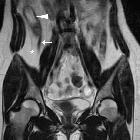

Crohn's disease in the appendix

MRI

MR enterography has become an increasingly important part of the management of patients with Crohn disease. MR enteroclysis may be attempted in select patients.

MR enterography (MRE)

Features of small bowel Crohn disease to be assessed on dedicated MRI study include:

- DWI: restrict diffusion is seen within the small bowel wall segments of active inflammation

- intramural edema

- better assessed on MRI T2 fat-saturated or low b-value DWI sequences

- increased T2 signal in the thickened bowel wall is particularly helpful in evaluating for acute inflammation

Mesenteric signs of inflammation include:

- engorged vasa recta: enlarged mesenteric blood vessels related to an inflamed bowel loop (comb sign)

- fibrofatty proliferation (creeping fat):

Extraintestinal involvement can be at least partially assessed on MR enterography, particularly, hepatobiliary disease (eg. gallstones) and sacroiliitis.

MRI pelvis

Crohn perianal disease is mostly characterized on imaging by perianal fistulas and is better evaluated using a dedicated MRI protocol for the anal canal.